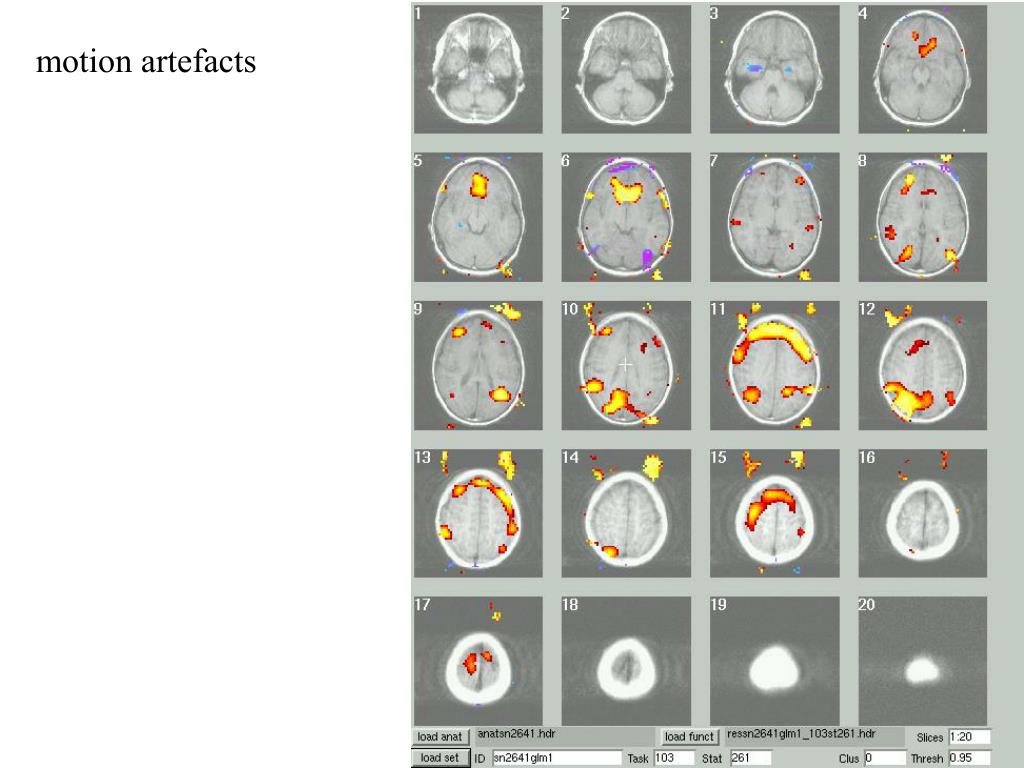

14. motion artefacts

15. motion artefacts